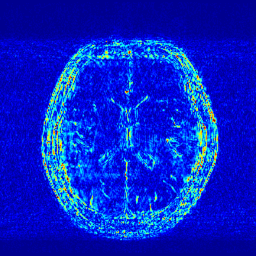

We illustrate with reconstructions for three CS-MRI methods: TLMRI (transform learning MRI) [25], PANO (patch-based nonlocal operator) [23] and GBRWT (graph-based redundant wavelet transform) [14]. The PANO and GBRWT models achieve impressive reconstruction qualities because they use an nonlocal prior and adaptive graph-based wavelet transform to exploit image structures. In TLMRI, the sparsifying transform learning and the reconstruction are performed simultaneously in more efficient way than DLMRI [24]. The three methods represent the state-of-the-art performance in the non-deep CS-MRI models. In Figure 2, we show the reconstructions error for zero-filled (itself a potential reconstruction “algorithm”), TLMRI, PANO and GBRWT on a complexed-valued brain MRI using 30%percent3030\% Cartesian under-sampling. The error display ranges from 0 to 0.2 with normalized data. The parameter setting will be elaborated in the Experiment Section V.

We also consider the deep learning DC-CNN model [26] as the guide module. We also give the reconstruction error in Figure 2. We observe the zero-filled, TLMRI, PANO, GBRWT and DC-CNN models all suffer the structural reconstruction errors, while the DC-CNN model achieves the highest reconstruction quality with minimal errors because of its powerful model capacity. Another advantage of this CNN model is that, once the network is trained, testing is very fast compared with conventional sparse-regularization CS-MRI models. This is because no iterative algorithm needs to be run for optimization during testing since the operations are a simple feed forward function of the input. We compare the reconstruction time of TLMRI, PANO, GBRWT and DC-CNN for testing for Figure 2 in Table I.

Figure 2: The reconstruction error of a brain MRI using zero-filled, TLMRI, PANO, GBRWT and DC-CNN under 1D 30%percent3030\% under-sampling mask.